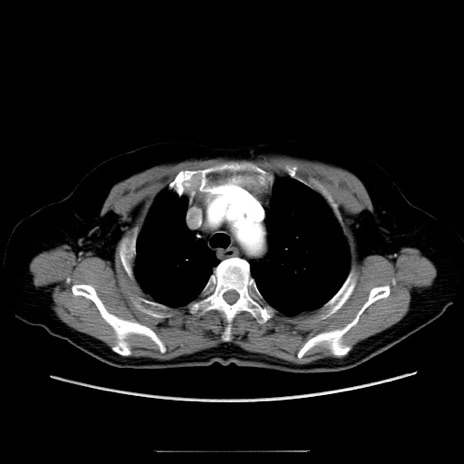

症例

冠状断像

【症例】70歳代女性

【主訴】お腹が張る

【現病歴】1週間くらい前から腹部膨満の自覚あり。昨日夜から増悪したため、本日救急外来受診。

【身体所見】意識清明、BT 36.5℃、BP 165/106mmHg、HR 80bpm、SpO2 98%、腹部:膨満、軟、自発痛・圧痛なし、触診にて不快感あり、腸蠕動音:減弱

【データ】WBC 12600、CRP 1.04